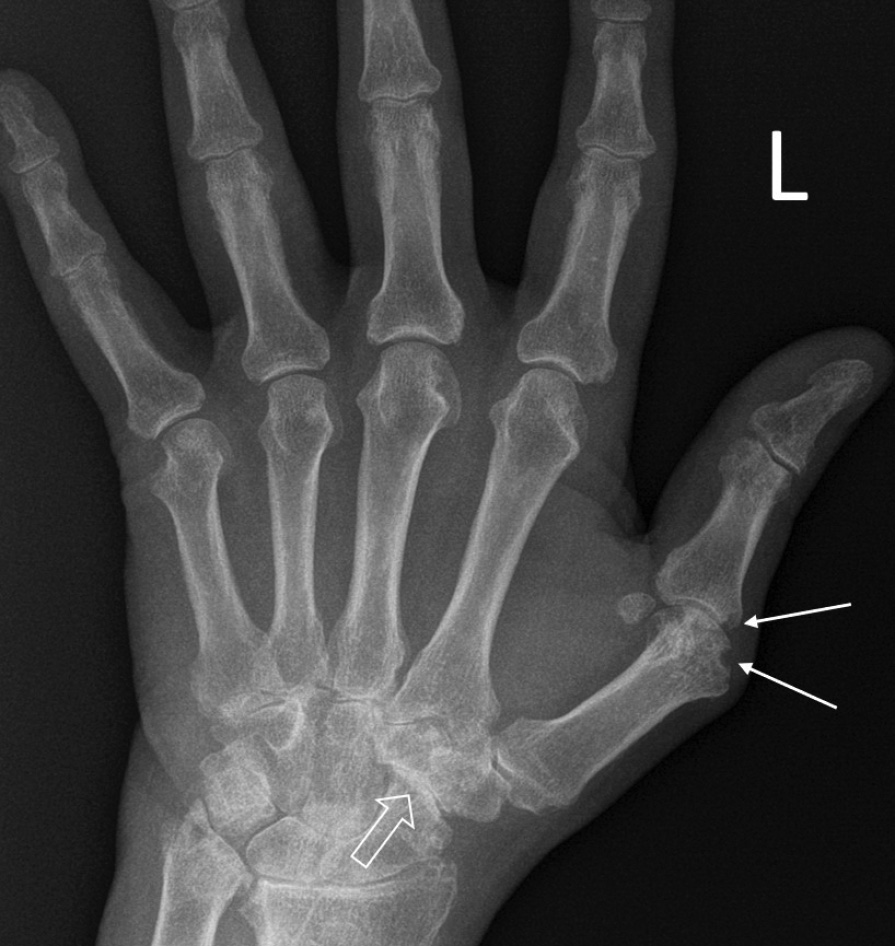

При компьютерной томографии органов грудной клетки данных за «свежие» очаговые и инфильтративные изменения не получено. Увеличения лимфатических узлов подмышечных областей, средостения, корней легких не выявлено. Отмечался усиленный грудной кифоз, обызвествление передней продольной связки, на всем уровне исследования определялись передне-боковые спондилофиты, а также анкилоз большинства реберно-поперечных суставов. По данным рентгенографии кистей (рис. 1, 2) и стоп (рис. 3, 4) диагностированы признаки эрозивного артрита, анкилоз суставов запястья. По данным МРТ крестцово-подвздошных суставов (КПС) определялся неравномерный анкилоз КПС, хрящи по суставным поверхностям неравномерной толщины, примерно на половине протяжении сустава отсутствуют, «суставной промежуток» облитерирован. Неравномерность и нечеткость контура суставных поверхностей за счет множества краевых эрозий справа, единичных – слева, с наличием остеокластоза, в нижнем отделе слева по смежным отделам определяются участки трабекулярного отека, данная находка клинически интерпретирована как двусторонний активный сакроилиит (рис. 5, 6).

Рис. 5. Магнитно-резонансная томография (Т2-взвешенное изображение в поперечной проекции). Протяженные участки анкилоза крестцово-подвздошных сочленений (толстые стрелки), эрозии суставных поверхностей (тонкие стрелки)

Рис. 6. Магнитно-резонансная томография (Т1-взвешенное изображение в косой корональной проекции). Протяженные участки анкилоза крестцово-подвздошных суставов (толстые стрелки), субхондральная киста правой латеральной массы крестца (тонкая стрелка). При магнитно-резонансной томографии крестцово-подвздошных сочленений с обеих сторон определяются крупные зоны анкилоза (суставные щели полностью облитерированы на 1/3 поверхности сустава справа, на 2/3 поверхности слева, что соответствует III рентгенологической стадии сакроилиита справа, IV стадии слева по Келлгрену). На остальных участках суставной хрящ неравномерно истончен, суставные поверхности неровные за счет множественных эрозий справа, единичных – слева. Определяются единичные мелкие (4 мм) субхондральные кисты справа

Ведущим диагнозом в течение всей истории заболевания был «анкилозирующий спондилоартрит, смешанная форма, HLA-B27-ассоциированный», поставленный на основании типичного поражения позвоночника с формированием деформаций (костный анкилоз в переднем отделе Th4 и Th7, множественные синдесмофиты в области передних углов тел позвонков). Заключение МРТ КПС типично для пациента с АС: двусторонний анкилоз КПС, множественные краевые эрозии, с наличием остеокластоза и признаками трабекулярного отека костной ткани, двусторонний сакроилиит. Клиническая картина, проявляющаяся болями воспалительного характера и скованностью в пояснично-крестцовом отделе позвоночника, нарушением объема движения в позвоночнике, была характерна для прогрессирования АС. Диагноз подтверждался наличием положительного гена HLA-B27 [2].